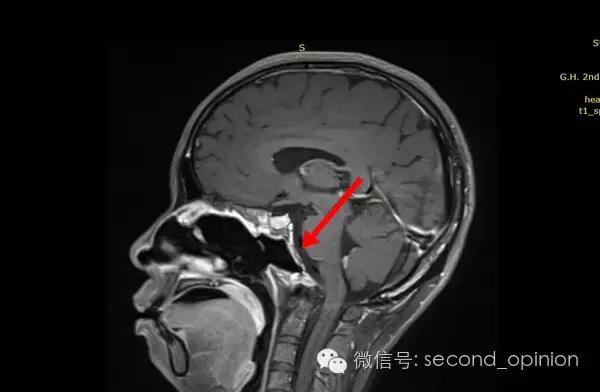

2014年12月 进行质子放射治疗。

日本国立癌症中心 2014年12月3日-12月31日

总剂量40GyE

2015年1月25日 对比质子治疗之前增强核磁共振影像无明显变化,脊索瘤放疗后变化缓慢,建议3月后继续复查。

2015年04月01日 对比增强核磁共振影像,同第一次复查。

2015年06月03日 对比增强核磁共振影像,对比第三次复查,肿瘤略有缩小。

质子治疗后第四次复查

目前患者生活质量良好,无复发转移。